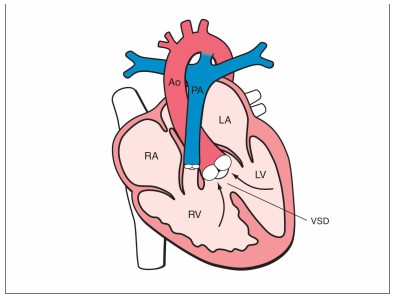

Các dị tật tim bẩm sinh thường gặp ở thai nhi như thông liên thất và tứ chứng Fallot

1. Thông liên thất (VSD) – dị tật phổ biến nhất

VSD là lỗ thông bất thường giữa hai buồng thất.

5. Tứ chứng Fallot (TOF)

Cấu trúc tim bị tứ chứng Fallot ở thai nhi, gồm thông liên thất và hẹp động mạch phổi

Gồm 4 dị tật kết hợp:

-

Thông liên thất

-

Hẹp động mạch phổi

-

Động mạch chủ cưỡi ngựa

-

Dày thất phải.